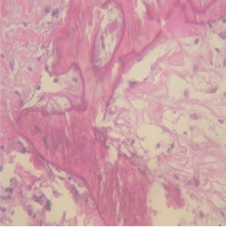

Transthoracic echocardiogram (Figure 2) (Figure 3) revealed a large atrial mass occupying the majority of the left atrium with dimensions 2,97 x 4,28cm with no obstruction of the mitral valve orifice. Transesophageal echocardiography (Figure 4) (Figure 5) confirmed presence of a large mass in the left atrium attached to the interatrial septum without prolaps of the tumour through the mitral valve. After coronary angiography and completion of preoperative dignostics, patient was transferred in another institution for surgical treatment. After surgical removal of the cardiac tumour, we received the histopathological material (Figure 6) which confirmed the diagnosis of cardiac myxoma. We continued with follow up of the patient by echocardiography control right after surgical treatment, as well as after 3 months, after 6 months, and after 12 months with no signs of tumor recurrence. She feels well and continues to take regularly antihypertensive drugs.7–9

Figure 6 Pathohistological finding after surgical extraction of the left atrial myxomas.